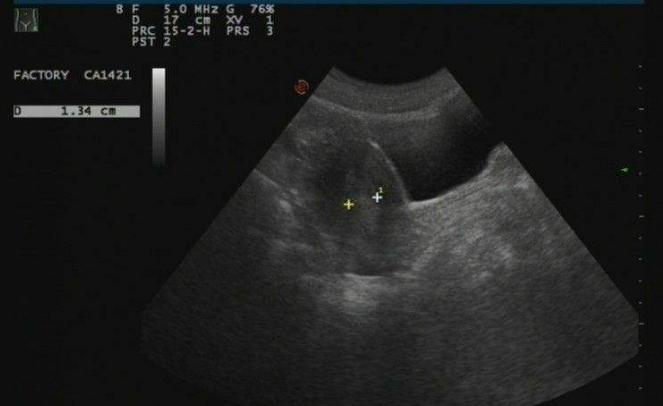

我和我老公结婚一年之后怀孕了,但是孕中期流产,结果又检查出子宫纵膈,当时做了宫腔镜下纵膈电切术,不过后面还是迟迟未孕,我又去医院做了子宫输卵管造影检查,发现双侧输卵管梗阻。